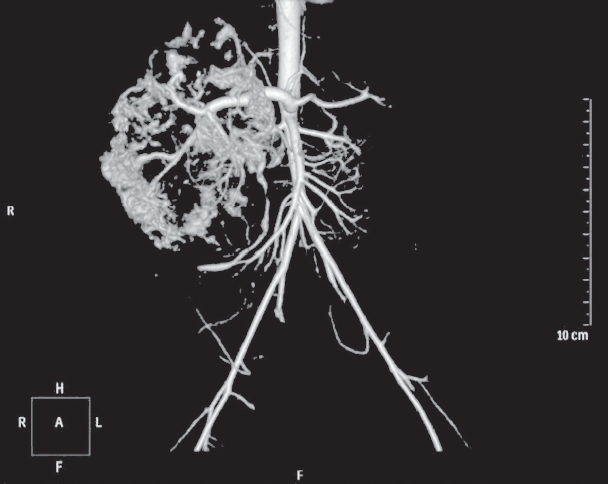

Проведено комплексное обследование: УЗИ органов брюшной полости (июнь 2019 г.) — в правой доле печени визуализируется объемное образование с неоднородной структурой, занимающее большую часть правой доли, с четкими границами и гиперэхогенными включениями. МСКТ с контрастным усилением (июнь 2019 г.) — КТ-картина образования, наиболее соответствующего сосудистому образованию — гемангиоме печени (рис. 4, 5).

Рис. 4. Компьютерная томограмма: объемное изображение васкуляризации образования

Fig. 4. CT: Image of tumor vascularization